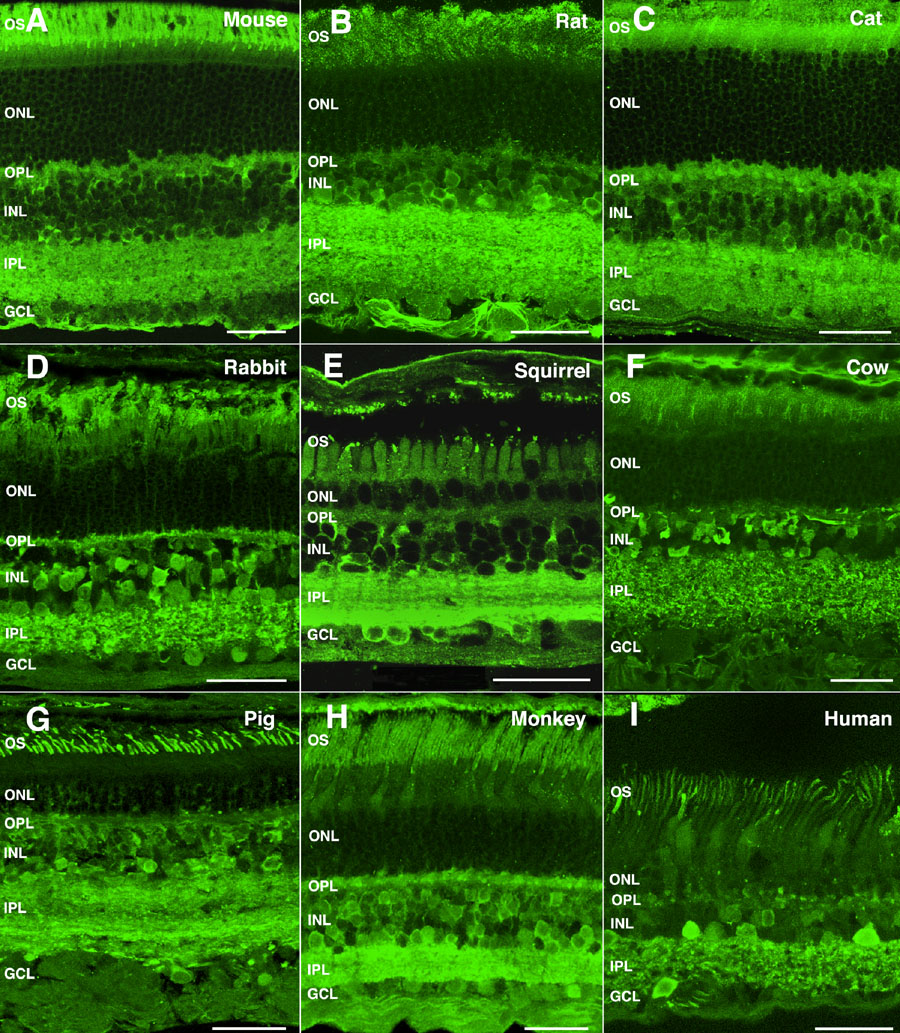

Figure 3. α-Synuclein immunoreactivity pattern in the retina of mammalian vertebrates

Shown are retinal sections immunolabeled for α-synuclein from (A) mouse, (B) rat, (C) cat, (D) rabbit, (E) squirrel, (F) cow, (G) pig, (H) monkey, and (I) human. The following abbreviations were used: outer nuclear layer (ONL), ganglion cell layer (GCL), inner nuclear layer (INL), outer plexiform layer (OPL), inner plexiform layer (IPL), and outer segments (OS). Each bars equals 40 μm.